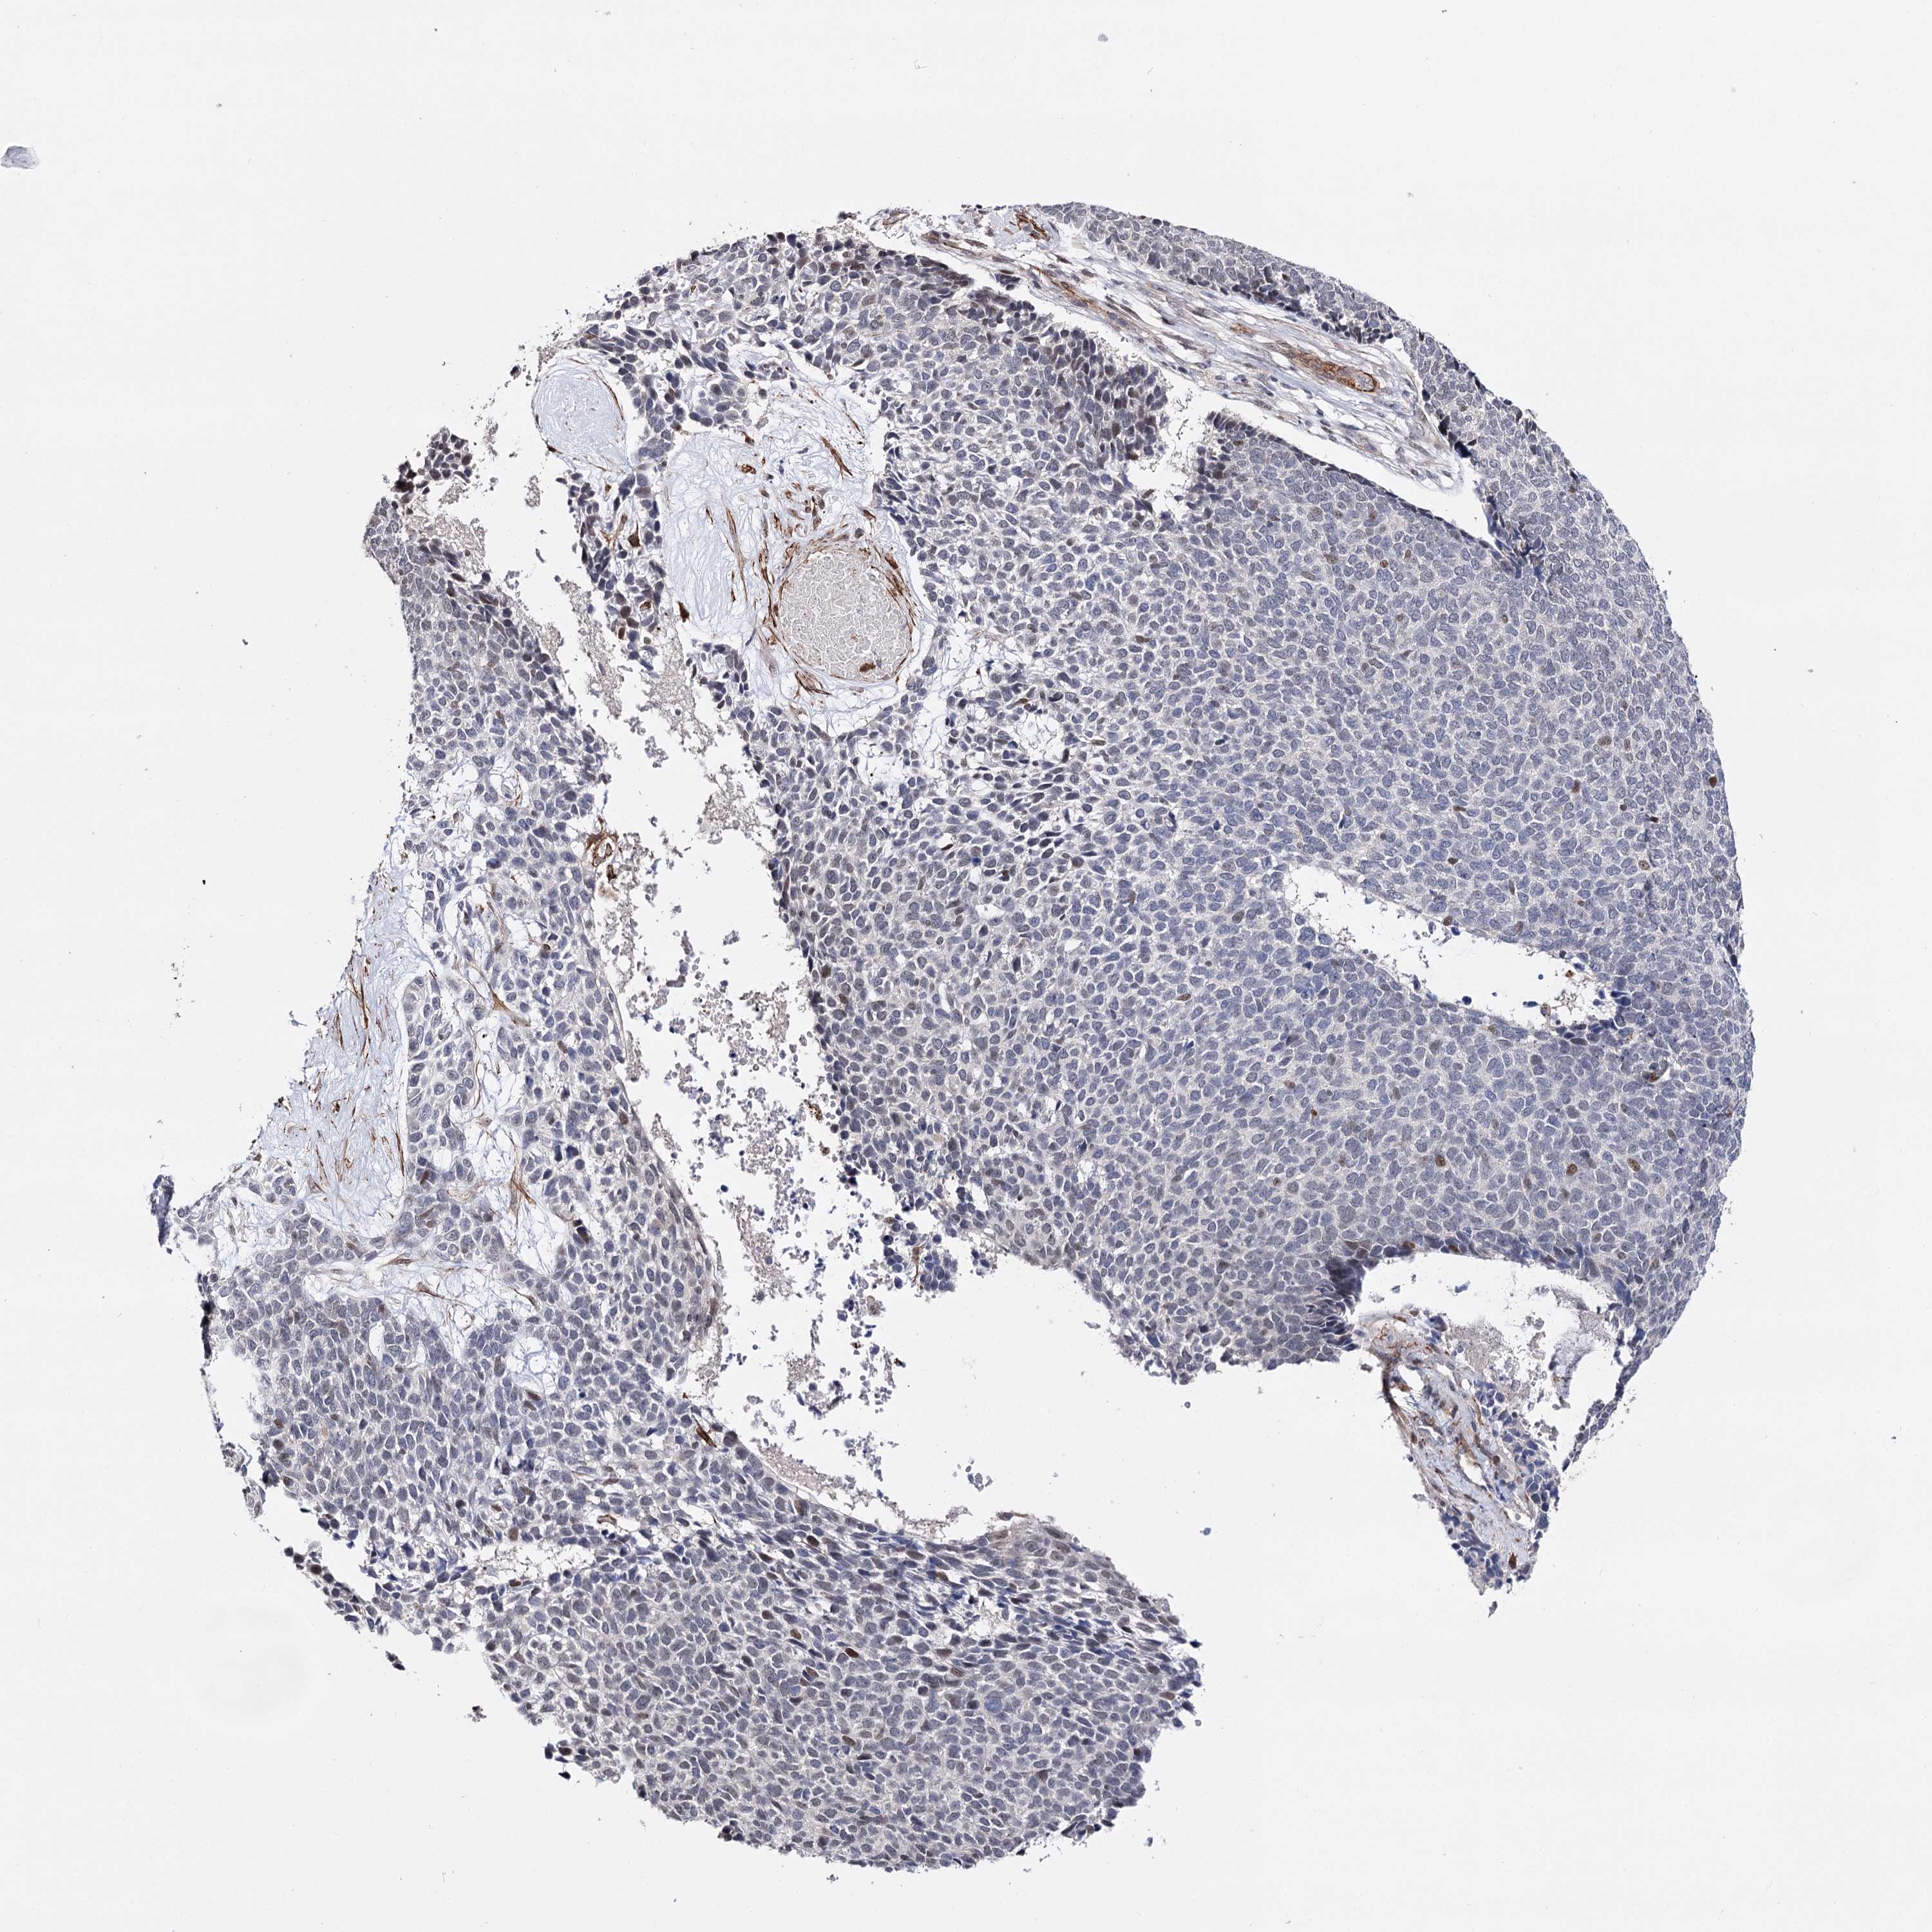

SKIN CANCER - Protein expressioni

A mouse-over function shows sample information and annotation data. Click on an image to view it in a full screen mode. Samples can be filtered based on level of antibody staining by selecting one or several of the following categories: high, medium, low and not detected. The assay and annotation is described here.

Each image is clickable and will lead to virtual microscopy that enables deeper exploration of all samples and also displays staining intensity scores, fraction scores and subcellular localization as well as patient and tissue information for each sample.

Antibody HPA038867

Squamous cell carcinoma, metastatic, NOS